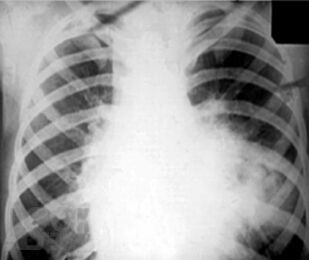

Рентгенологические синдромы при туберкулезе органов дыхания

В предлагаемом учебно-методическом пособии рассматриваются основные рентгенологические синдромы при патологии органов дыхания, а также частные вопросы рентгенологической диагностики туберкулеза органов дыхания.